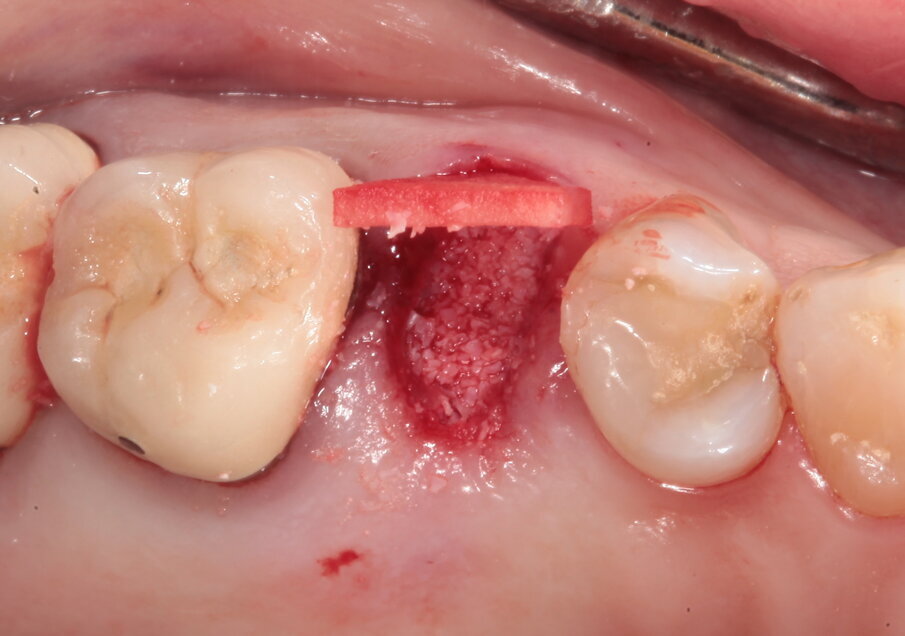

Il piano di trattamento prevede quindi l’estrazione del 25 giudicato non mantenibile, la preservazione dell’alveolo post estrattivo, l’inserimento differito di un impianto e il suo carico una volta terminato il processo di osteointegrazione. Per quanto riguarda l’elemento 24, si programma la terapia endodontica e la successiva ricostruzione diretta. Viene effettuata un’estrazione atraumatica del 25, la rimozione del tessuto infiammatorio periapicale e il posizionamento di un sostituto osseo addizionato con acido ialuronico reticolato ad alto peso molecolare (HyaDENT BG) al fine di ottenere una più rapida stabilizzazione del coagulo ed una buona stabilità dell’innesto, determinanti per il mantenimento del volume ottimale. Questo viene poi coperto con una membrana di collagene suino imbustata al di sotto dei tessuti vestibolari e palatali (Figg. 6-10).